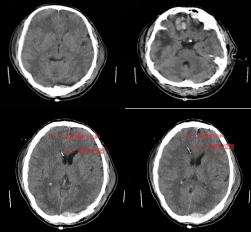

由于血肿位置特殊,手术区域临近重要血管,如若损伤可能危机生命,较普通手术有一定难度。由于术前手术医师的充分准备和术中对重要血管的保护,经过五个小时的手术治疗,手术顺利成功完成,患者术后转入了医院重症监护室进一步监护治疗。术后复查颅脑CT发现,患者原本双侧额叶的脑挫伤出血增多,为保证患者生命安全和避免多次手术及巨额治疗费用,经科室讨论,放弃以往的“骨瓣减压术”手术方式而选择了现国内外推荐可行的“颅内压监测/脑室外引流术”,该手术技术在神经外科已成熟并已经成功救治多例患者。主管医生再次向家属详细 病情及下一步治疗方案并同时了解到患者家庭经济困难,于是安抚患者家属的同时宣传阿坝州医保政策,包括大病医疗补助,水滴筹多种方式来解决经济困难以救治患者,患者家属焦虑的心情得以平复,经过商议和医生们的充分准备,患者顺利进行了第二次手术治疗。

患者在第二次手术治疗后复查恢复情况良好,患者手术中置入了颅内颅内压探头,该探头对患者颅内压进行了实时监测,保障了患者顺利度过危险期,病情逐渐平稳。住院期间政府相关部门及医院领导多次到病房关心慰问患者,经过医院医护人员对患者的精心救治及家属的辛勤照顾下,患者恢复良好,顺利出院。